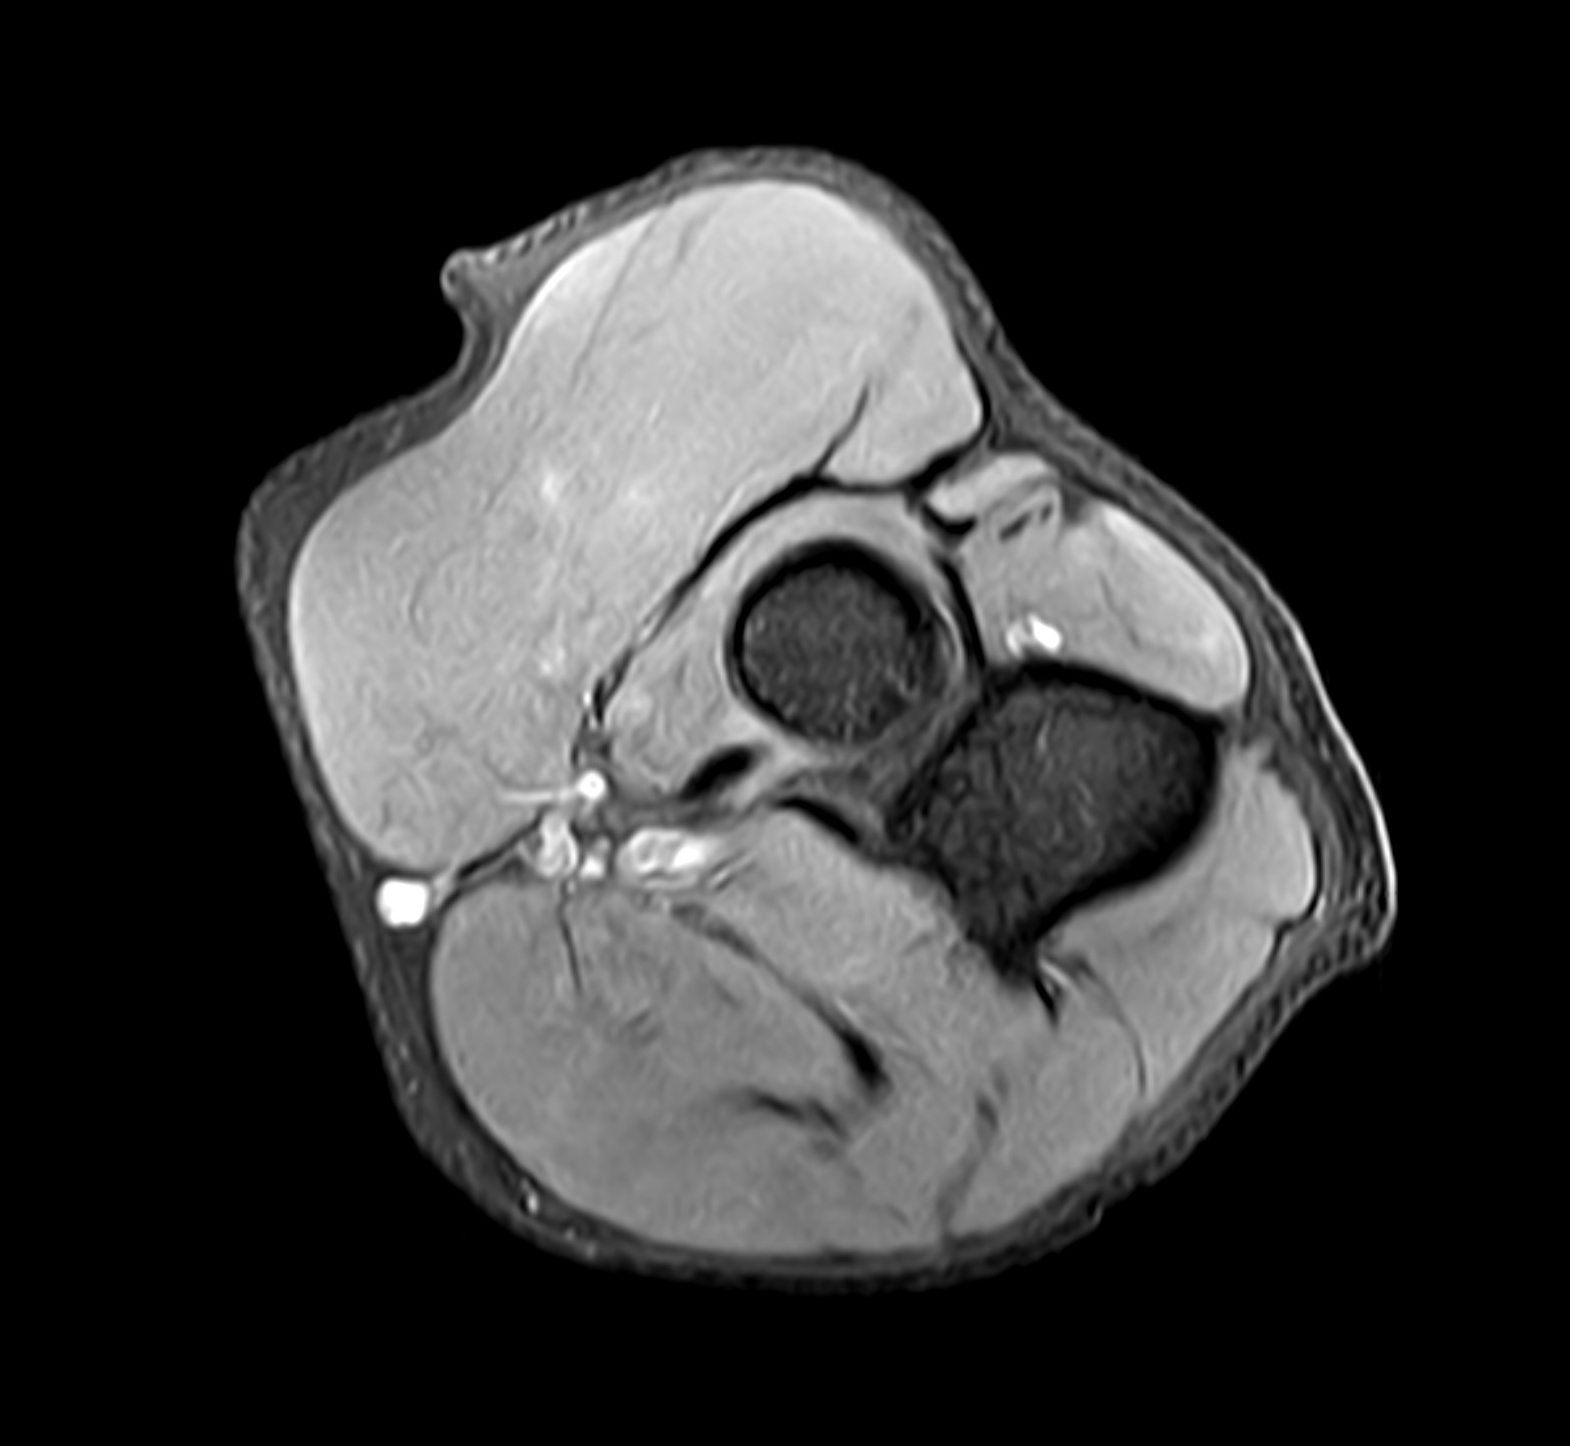

Elbow pain and related symptoms may arise from various causes, ranging from mild overuse to joint inflammation or nerve compression. Magnetic resonance imaging (MRI) is particularly valuable when other diagnostic methods like X-ray or ultrasound have not provided clear answers. MRI offers detailed images of both bone and soft tissue, making it possible to identify early changes or hidden injuries.

- Tennis elbow (lateral epicondylitis) – an overuse injury where tendon attachments on the outer elbow become inflamed. MRI can confirm the diagnosis and show the extent of tendon and soft tissue involvement.

- Golfer’s elbow (medial epicondylitis) – similar to tennis elbow but located on the inner side of the elbow. MRI helps rule out other structural issues and assess the degree of inflammation.

- Inflammatory joint diseases (arthritis or bursitis) – in suspected cases of rheumatoid arthritis or bursitis, MRI can identify swelling, joint fluid, synovitis, and other early inflammatory changes.

- Nerve entrapment – such as ulnar nerve compression at the elbow (cubital tunnel syndrome), which can cause numbness, tingling, and weakness in the forearm and hand. MRI can visualize nerve compression or surrounding swelling.

- Degenerative changes and osteoarthritis – MRI reveals cartilage loss, joint space narrowing, and other degenerative changes that may not be visible on standard radiographs.

- Tendon and muscle injuries – including partial tears, full ruptures, or chronic overuse at tendon insertions. MRI provides a clear view of the extent and location of the injury.

- Cartilage or ligament injuries – may occur with twisting injuries or trauma. MRI is superior in detecting such injuries, especially if they are subtle or not visible with other imaging methods.

- Calcific deposits or fluid accumulation – MRI can detect calcium deposits in tendons and bursae, as well as localized fluid collections that may cause pain and restricted movement.